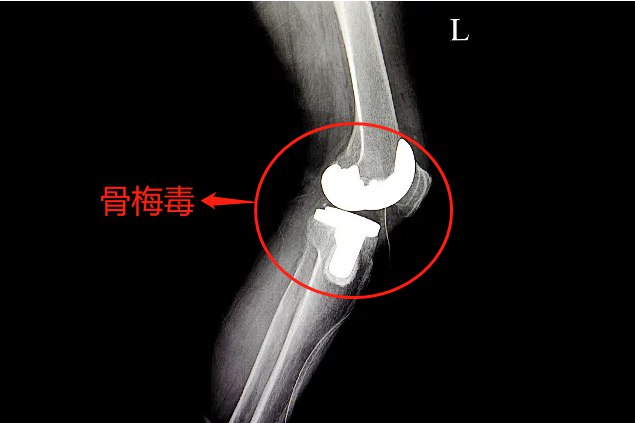

骨梅毒是因为梅毒螺旋体链球菌侵害骨骼所导致的传染性疾病。

骨梅毒是通过性行为感染梅毒螺旋体所引起,其中二期梅毒和三期梅毒都可能会出现骨的病变,形成骨梅毒症状。两期骨梅毒的共同症状为骨痛,基本会出现骨膜炎、骨炎、骨髓炎的病变,好发于长骨。另外患者还可以出现关节炎、滑囊炎、腱鞘炎,主要发生于四肢的大关节。如在上腭或者鼻骨出现树胶肿,可引起马鞍鼻、上腭破溃,最终形成溃疡。